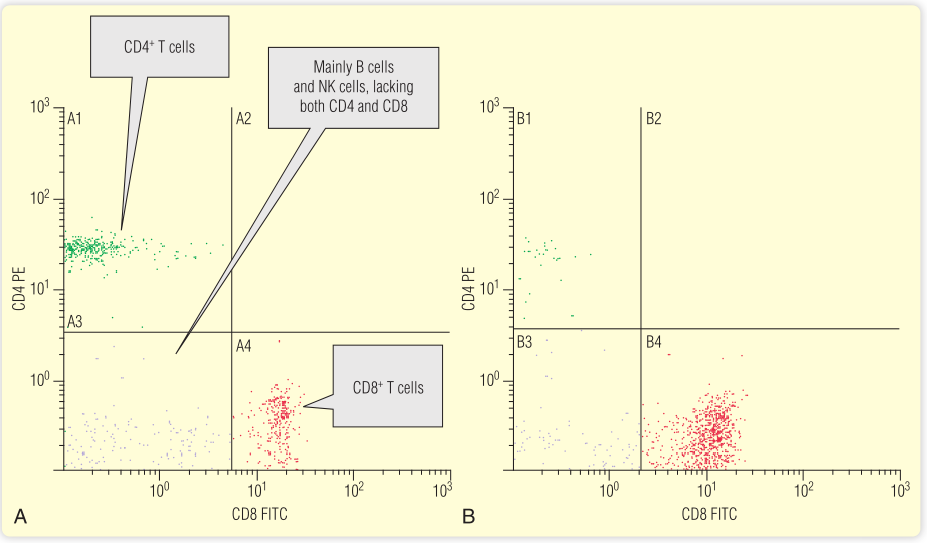

流式细胞术是一种用计数表达抗原的细胞的技术。这些细胞被细胞表面抗原特异性抗体染色。抗体被偶联到特定的荧光试剂,如FITC(还有其他几种不同颜色的荧光可供选择),然后通过流式细胞仪。染色细胞的数量可以计数,例如CD4+T细胞的数量(Fig 5.7;另一个例子见第35章)。

Fig 5.7 流式细胞仪“散点图”